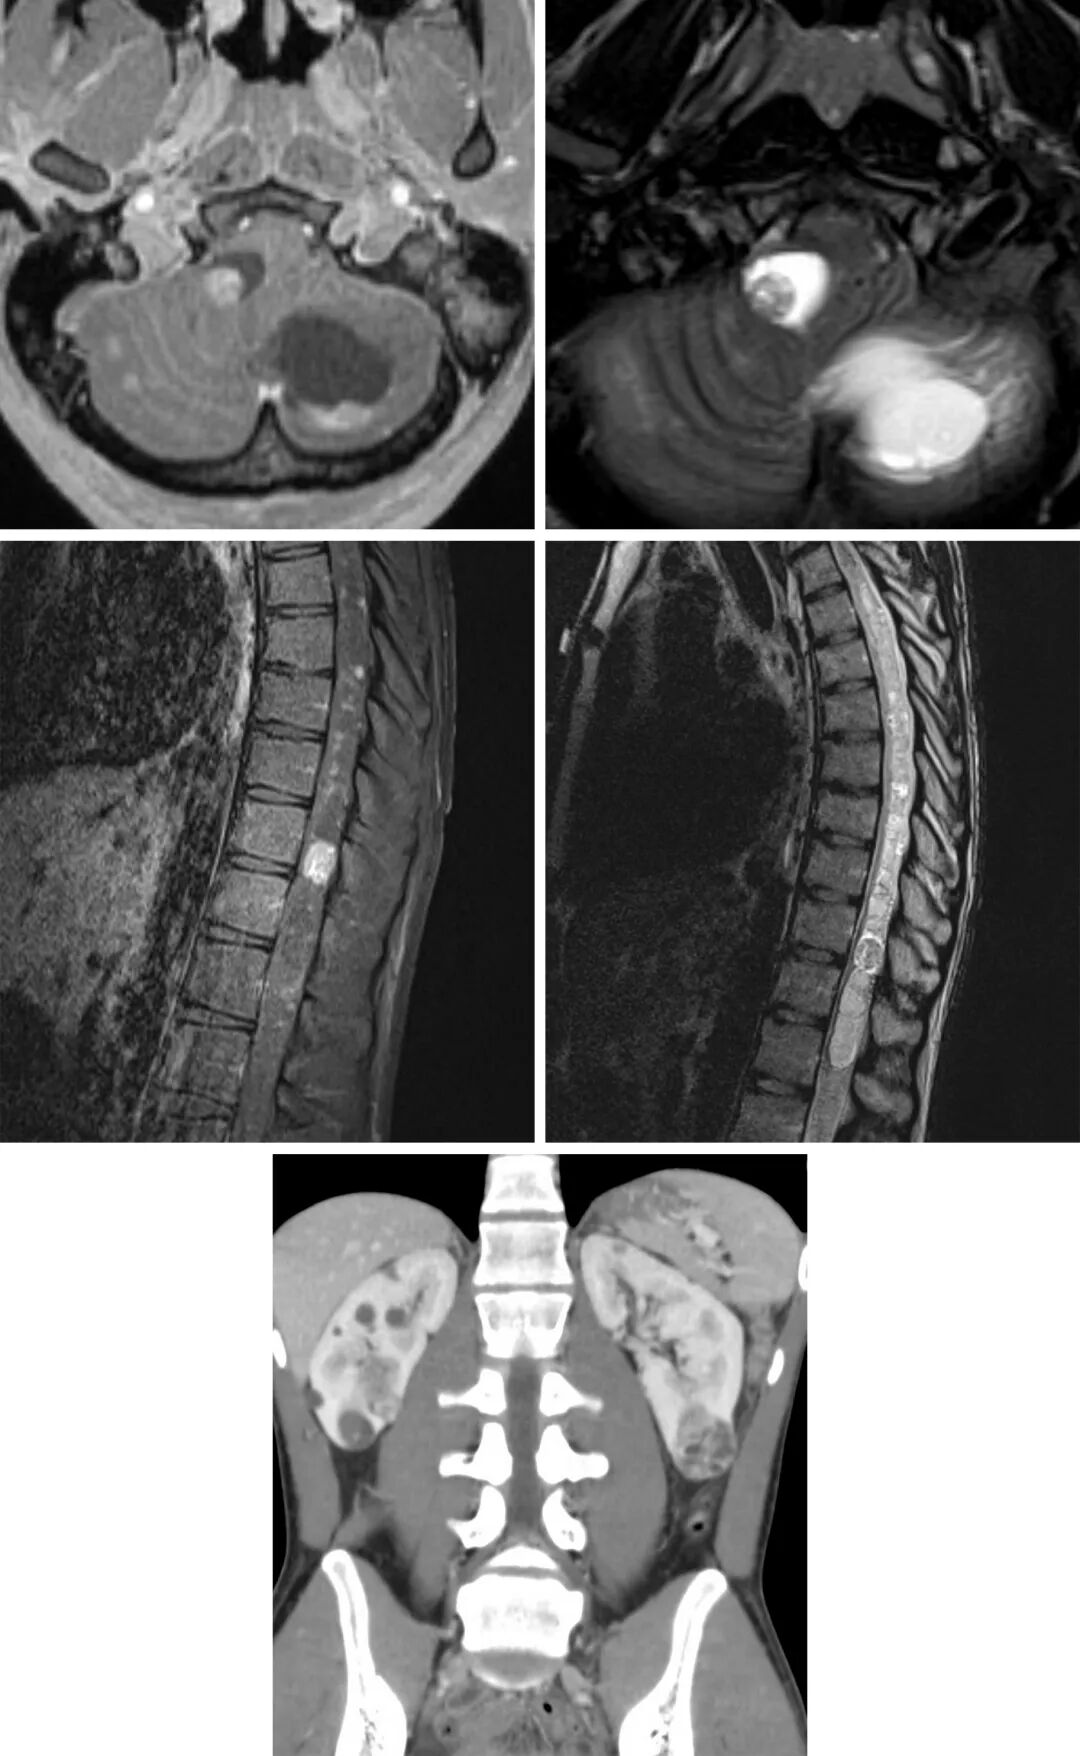

图1:血管母细胞瘤在T2加权相上呈典型的囊性改变(右上);在T1加权相上可见壁结节(左上);T1增强加权相上壁结节明显强化,囊壁无明显强化(下)。

MRI

T1加权相:等信号结节,可见流空效应

T2加权相:高信号的囊变和结节,可能有高信号的瘤周水肿

FLAIR相:高信号的囊变和结节,可能有高信号的瘤周水肿

T1增强相:结节明显强化;囊性部分无强化,囊壁常无强化效应